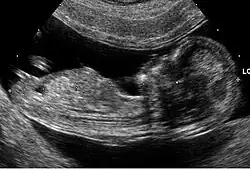

La ecografía genética o simplemente eco genético es un tipo de ultrasonido obstétrico que consiste en la valoración del feto para demostrar o descartar cualquier alteración anatómica o del estado de la salud del medio intrauterino reportando hallazgos o marcadores que pueden orientar en la identificación de fetos que tengan alteraciones cromosómicas.[1] La ecografía genética no tiene una precisión absoluta, de manera que una ecografía normal no garantiza que el bebé sea normal y hallazgos considerados anormales por un ecografista no garantiza que el bebé no sea normal.[1]

El eco genético suele realizarse en el segundo trimestre con el fin de detectar anomalías, incluyendo defectos estructurales así como también defectos no estructurales, que son los llamados marcadores ecográficos.[6] Los más comunes observados en las ecografías del segundo trimestre, son el engrosamiento del pliegue nucal, el intestino hiperecogénico, el acortamiento de los huesos largos (principalmente el húmero y fémur), la pielectasia renal, los focos ecogénicos intracardíacos y los quistes de los plexos coroideos.[7] Muchos de estos hallazgos, sin embargo, pueden conseguirse de manera aislada en fetos euploides, y aparecer sólo de manera temporal, por tanto la interpretación de los mismos debe ser cuidadosa.

El avance de la ecografía, con las mejoras en la resolución de imagen, ha permitido que sea posible determinar cada vez con mayor precisión el diagnóstico prenatal de defectos a nivel facial, incluyendo el labio leporino.[8]